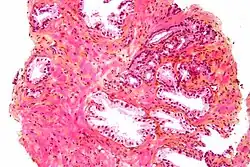

The prostate consists of glandular and connective tissue.[2] Tall column-shaped cells form the lining (the epithelium) of the glands.[2] These form one layer or may be pseudostratified.[4] The epithelium is highly variable and areas of low cuboidal or flat cells can also be present, with transitional epithelium in the outer regions of the longer ducts.[10] Basal cells surround the luminal epithelial cells in benign glands. The glands are formed as many follicles, which drain into canals and subsequently 12–20 main ducts, These in turn drain into the urethra as it passes through the prostate.[4] There are also a small amount of flat cells, which sit next to the basement membranes of glands, and act as stem cells.[2]

The connective tissue of the prostate is made up of fibrous tissue and smooth muscle.[2] The fibrous tissue separates the gland into lobules.[2] It also sits between the glands and is composed of randomly orientated smooth-muscle bundles that are continuous with the bladder.[11]

Over time, thickened secretions called corpora amylacea accumulate in the gland.[2]

Microscopic glands of the prostate -

Microanatomy of a prostatic gland, showing both luminal cells and surrounding basal cells. H&E stain. -